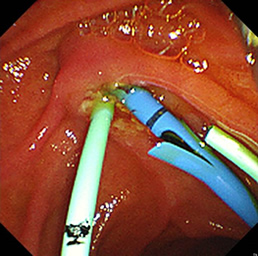

内視鏡的乳頭括約筋切開術

高周波電流で十二指腸乳頭部(胆管開口部)を一部凝固切開し、胆管結石を取り出します。

急性胆管炎の治療の際は、専用のバスケットカテーテルで総胆管内の胆汁を十二指腸や体外に排出できるようにステントを揷入留置します。

内視鏡的乳頭括約筋切開術(EST)